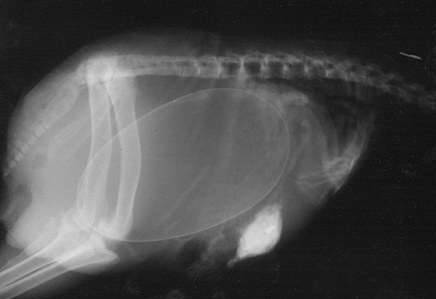

▼怀孕的猫咪